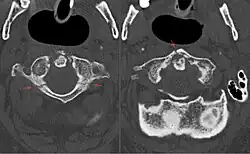

Uma fratura de Jefferson é uma fratura da primeira vértebra (atlas). É classicamente descrita como uma fratura em quatro partes dos arcos posterior e anterior do atlas,[1] embora ela também possa aparecer como uma fratura em duas ou três partes. A fratura pode resultar de compressão da segunda vértebra ou hiperextensão do pescoço, causando uma fratura posterior, que pode estar acompanhada por fraturas de outras partes da coluna cervical.[1]

Somente cerca de 1-2% das fraturas espinhais são fraturas do atlas, das quais cerca de um terço são fraturas clássicas de Jefferson com 4 fragmentos.[2] É causada por uma força potente axial (longitudinal, ao longo da coluna vertebral) sobre o crânio, que é transmitida aos côndilos laterais, quebrando o anel do atlas em seu local mais fraco, levando os fragmentos de fratura para fora. Frequentemente isto ocorre em lesões durante banhos, quando a pessoa salta de cabeça em águas rasas.

A confirmação radiológica se dá através de uma radiografia com a boca aberta.